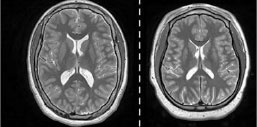

МРТ позволяет выявлять аномалии мозга у недоношенных детей

Методика количественной МРТ позволяет выявить патологические изменения в структуре мозга у недоношенных детей, которые в подростковом возрасте могут привести к развитию таких состояний, как аутизм или церебральный паралич. Результаты исследования были опубликованы в журнале Radiology.

Ученые считают, что аномалии развития мозга у недоношенных детей могут быть определены с помощью многопараметрической количественной МРТ и это позволит проводить своевременную терапию.

В текущем исследовании группа доктора Макнотона использовала количественную МРТ для оценки мозга недоношенных подростков. Было проведено исследование группы подростков (368 человек) в возрасте от 14 до 16 лет. У 252 детей развитие было нормальным, а 116 имели отклонения. Ученые сравнивали такие показатели, как объем мозга и плотность протонов, между двумя группами, а также между мальчиками и девочками.

Как показало исследование, у подростков, у которых было атипичное неврологическое развитие, на количественной МРТ отмечались небольшие различия в белом веществе, связанные с плотностью протонов, что соответствовало меньшему количеству свободной воды. В начале исследования ELGAN-ECHO исследователи собрали образцы пуповины и крови у недоношенных детей.